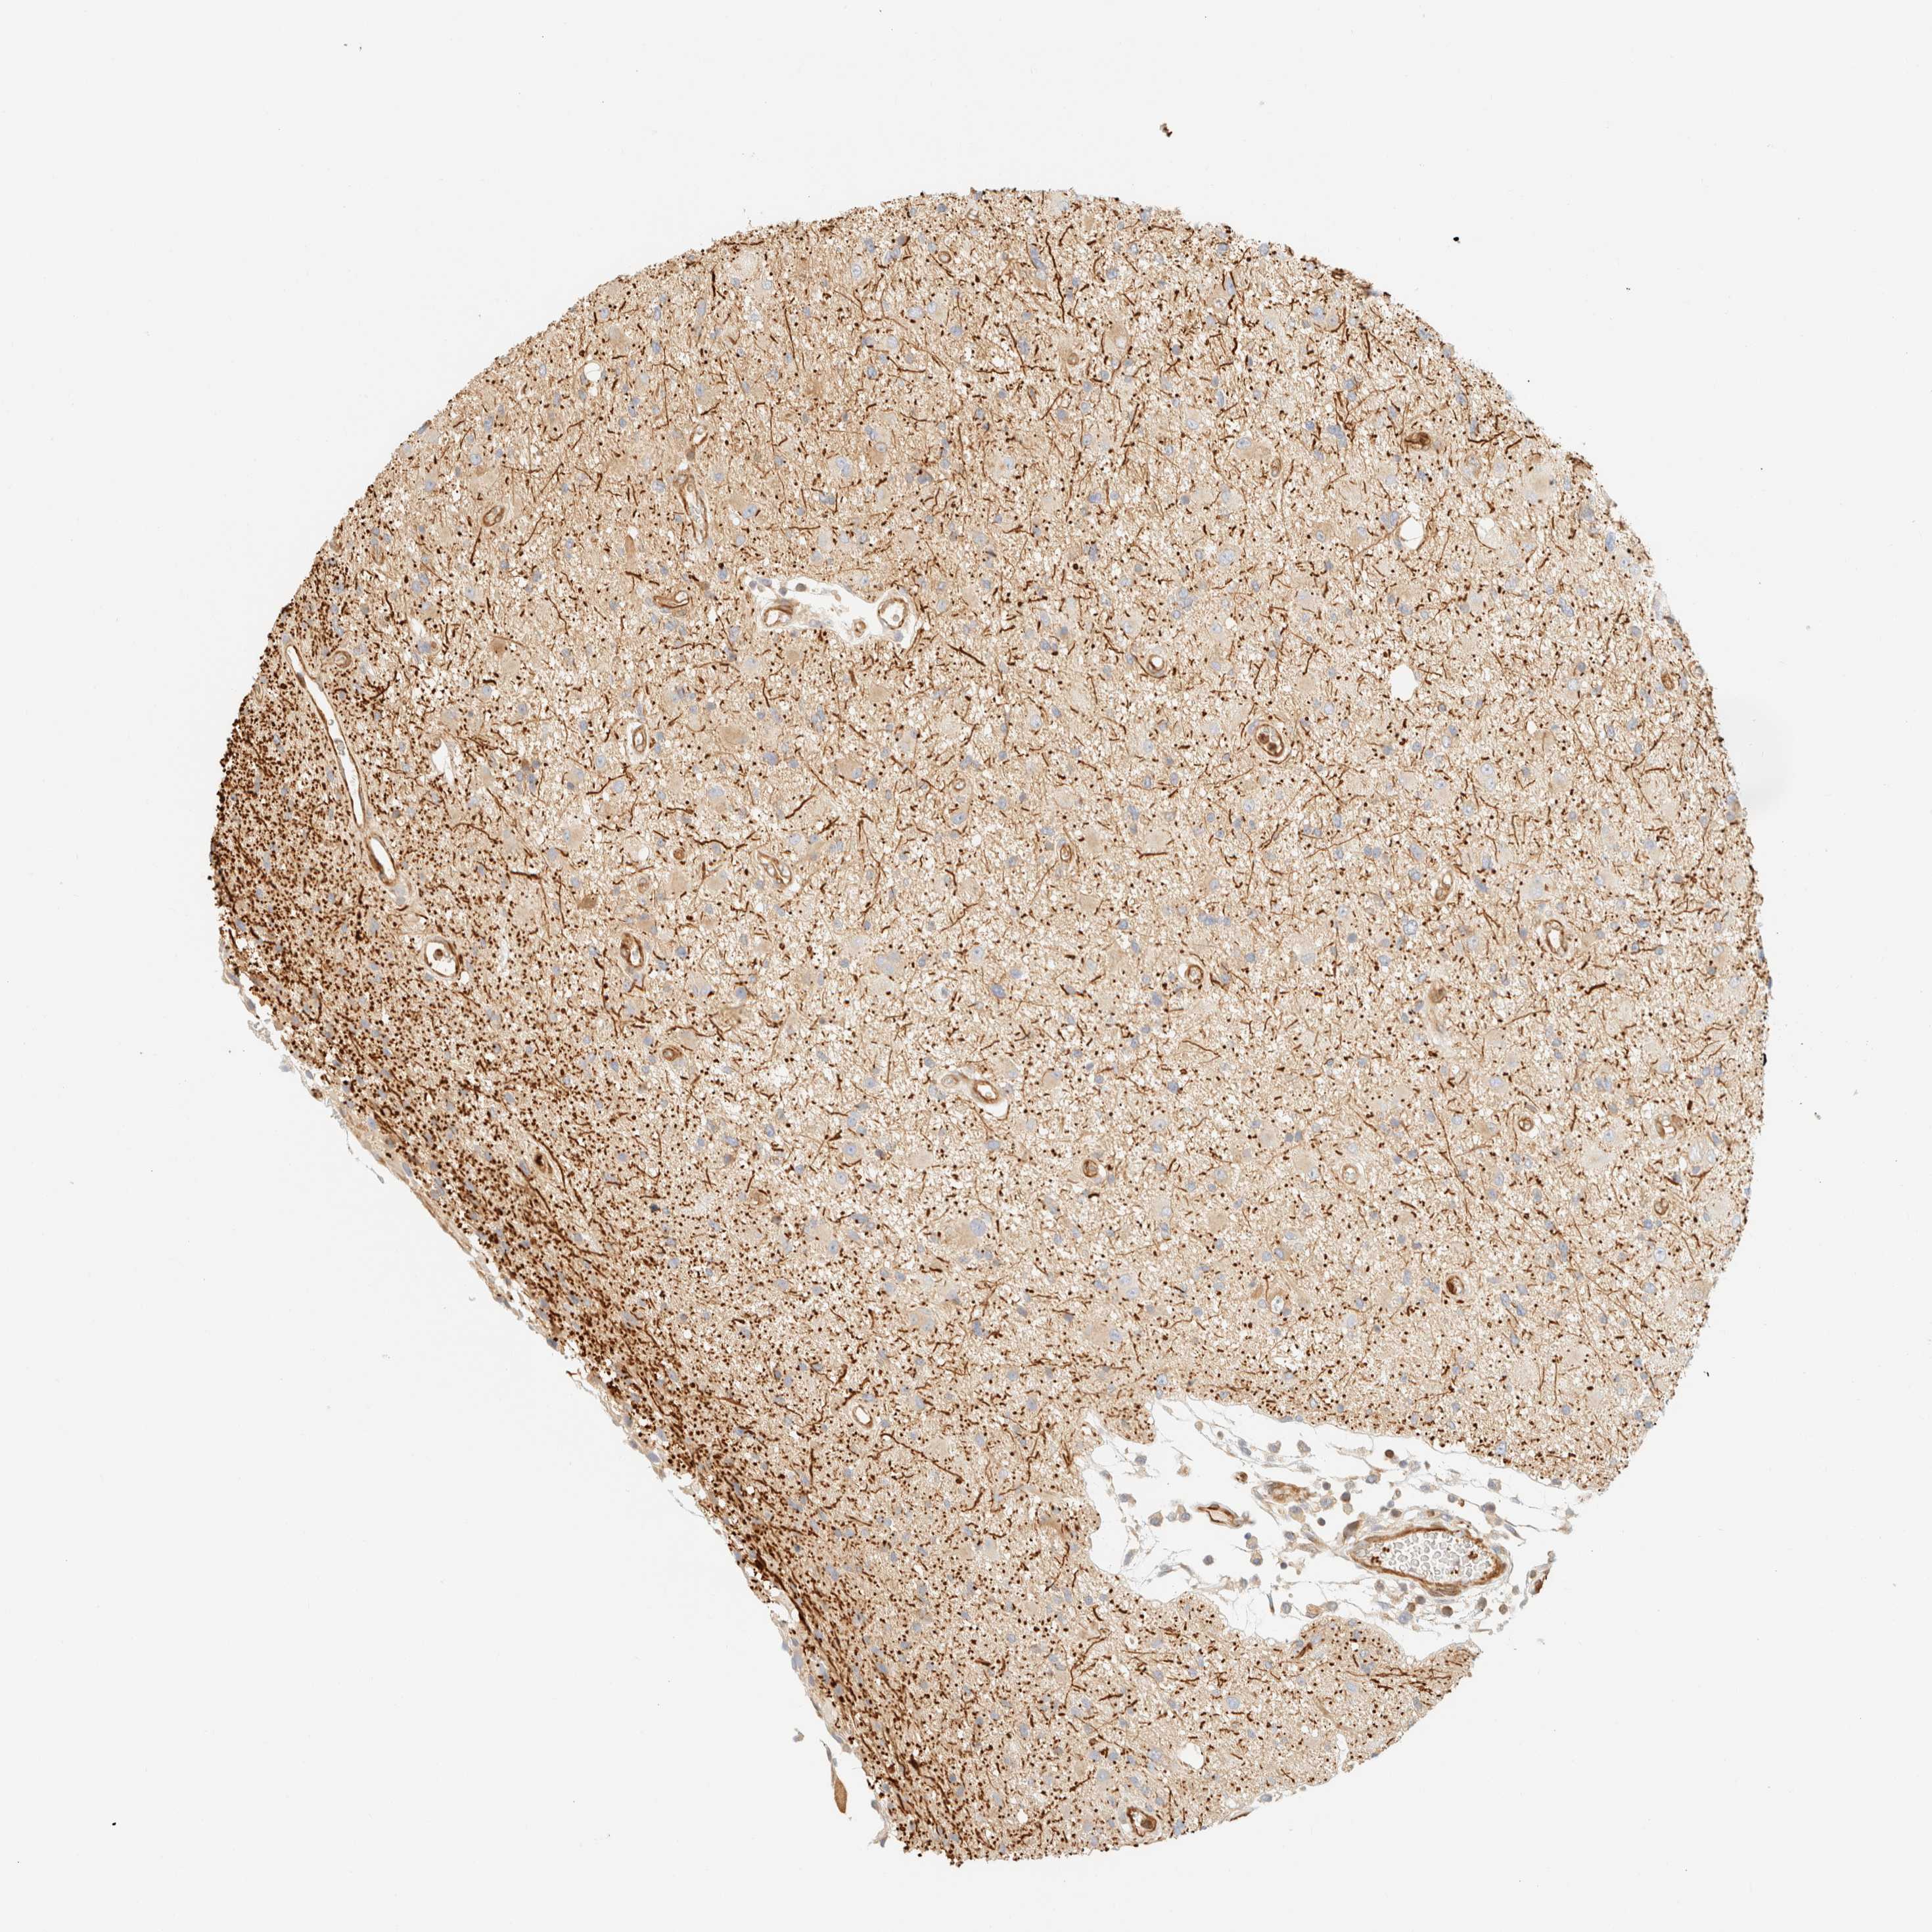

GLIOMA - Protein expressioni

A mouse-over function shows sample information and annotation data. Click on an image to view it in a full screen mode. Samples can be filtered based on level of antibody staining by selecting one or several of the following categories: high, medium, low and not detected. The assay and annotation is described here.

Note that samples used for immunohistochemistry by the Human Protein Atlas do not correspond to samples in the TCGA dataset.

Antibody stainingi

Antibody staining in the annotated cell types in the current human tissue is reported as not detected, low, medium, or high, based on conventional immunohistochemistry profiling in selected tissues. This score is based on the combination of the staining intensity and fraction of stained cells.

Each image is clickable and will lead to virtual microscopy that enables deeper exploration of all samples and also displays staining intensity scores, fraction scores and subcellular localization as well as patient and tissue information for each sample.

Antibody HPA024524

Antibody HPA053090

Staining

High

Medium

Low

Not detected

Intensity

Strong

Moderate

Weak

Negative

Quantity

>75%

75%-25%

<25%

None

Location

Nuclear

Cytoplasmic/membranous

Cytoplasmic/membranous,nuclear

Glioma, malignant, High grade

Glioma, malignant, Low grade